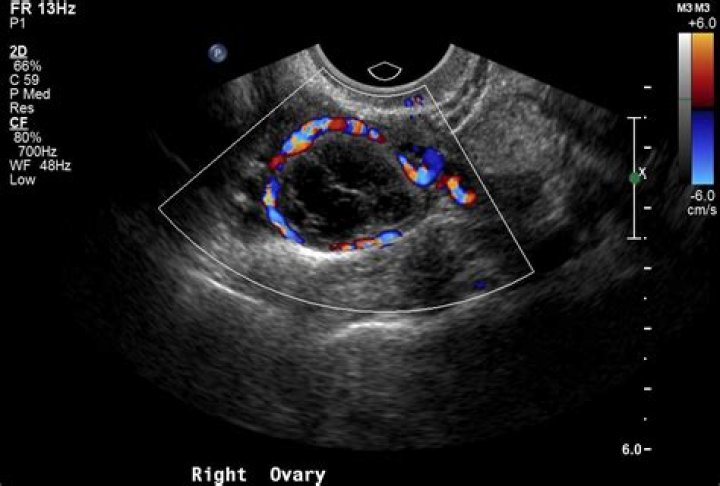

What does red mean on an ultrasound?

By definition, flow towards the transducer is depicted in red while flow away from the transducer is shown in blue. Different shades of red and blue are used to display velocity. Lighter shades of color are assigned to higher velocities.

However, to evaluate the presence and direction of blood flow in the heart and vessels, color Doppler ultrasound has been used. Color Doppler displays blood flow in two basic colors. Red or Red-Orange displays blood flowing towards the top of the screen, and Blue displays flow towards the bottom of the screen.

What do red and blue colors mean on ultrasound?

Vessels in which blood is flowing are colored red for flow in one direction and blue for flow in the other, with a color scale that reflects the speed of the flow. Because different colors are used to designate the direction of blood flow, this Doppler technique simplifies interpretation of the ultrasound data.

A third color, usually green or yellow, is often used to denote areas of high flow turbulence. These colors are user-definable and may be reversed, however this is generally inadvisable as it may confuse later readers of the images.

What do colors on an ultrasound mean?

Typically, red and blue colors are used to highlight the blood flow in one direction or the other regarding the probe's position. The speed of the blood flow is shown with a color scale. Usually, blood flow away from the probe is shown in blue, while blood flow toward the probe is red.

What do malignant ovarian cysts look like on ultrasound?

The most consistent sonographic signs of malignancy appears to be the presence of papillary excrescences > 3 mm along the internal wall of an ovarian mass and the presence of a solid component21.